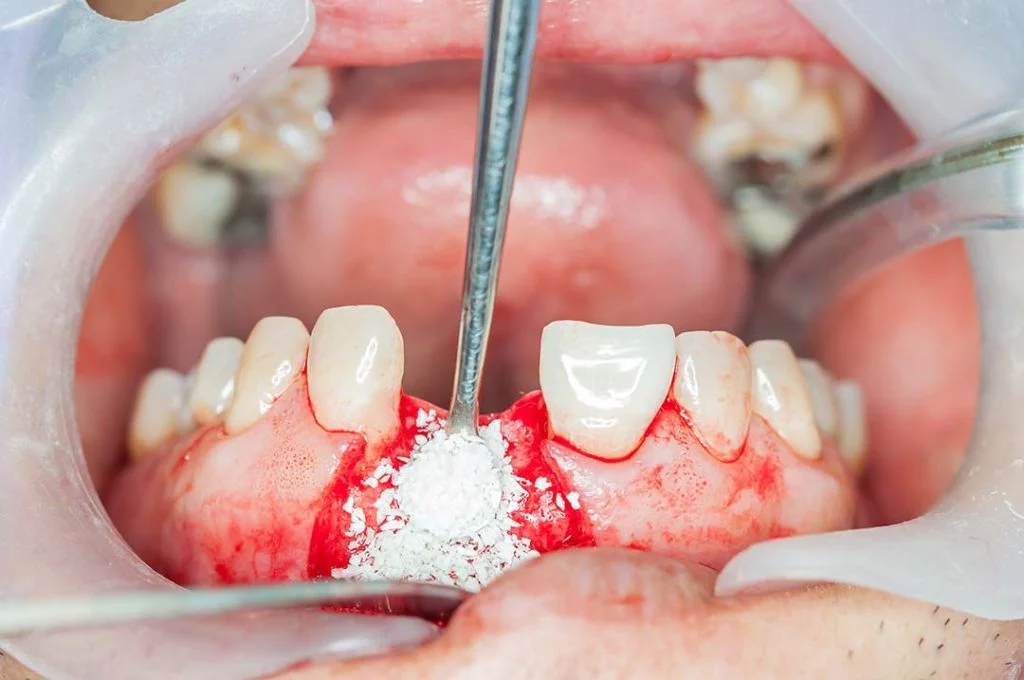

- Si inizia con una piccola incisione nella gengiva per accedere all’osso sottostante. Una volta individuata l’area da trattare, si inserisce il materiale da innesto.

- Il materiale osseo viene inserito in forma di particelle o blocchetti, a seconda della tecnica. Viene poi protetto con una membrana (resorbibile o non resorbibile) che ne facilita la stabilità e l’attecchimento.

- Innesto eterologo: l’osso proviene da un’altra specie (solitamente bovina), è trattato per essere sterile e biocompatibile. È molto usato per piccoli difetti ossei e ha il vantaggio di evitare un secondo intervento.

- Innesto sintetico: realizzato in laboratorio con materiali come l’idrossiapatite o fosfato di calcio. È biocompatibile e spesso combinato con osso naturale per una migliore osteointegrazione.